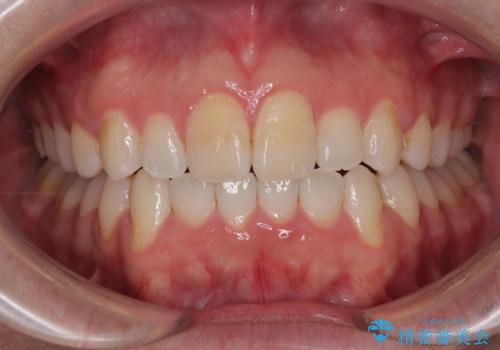

マウスピース矯正と迷った結果…管理のしやすさで選んだクリアブラケット矯正の症例

- 1年2ヶ月